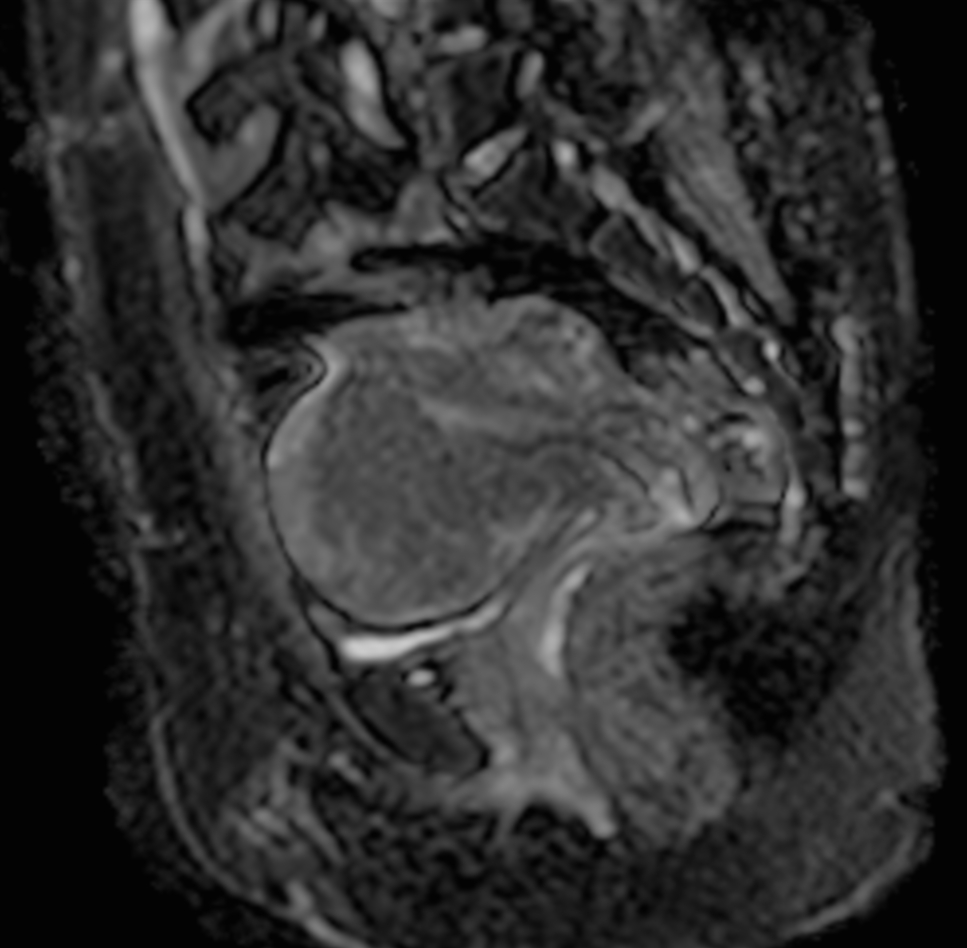

Sagittal T2w TSE